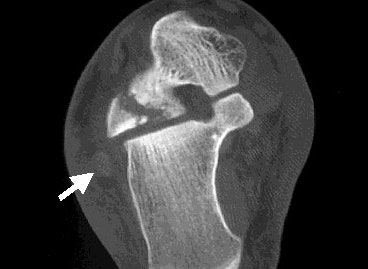

| Axial CT scan shows that the largest fracture fragment is displaced 3-4 mm posterolaterally. The peroneal tendons (white arrow) do not appear to be affected by the fracture fragments. Images courtesy of Dr. Douglas Beall. |